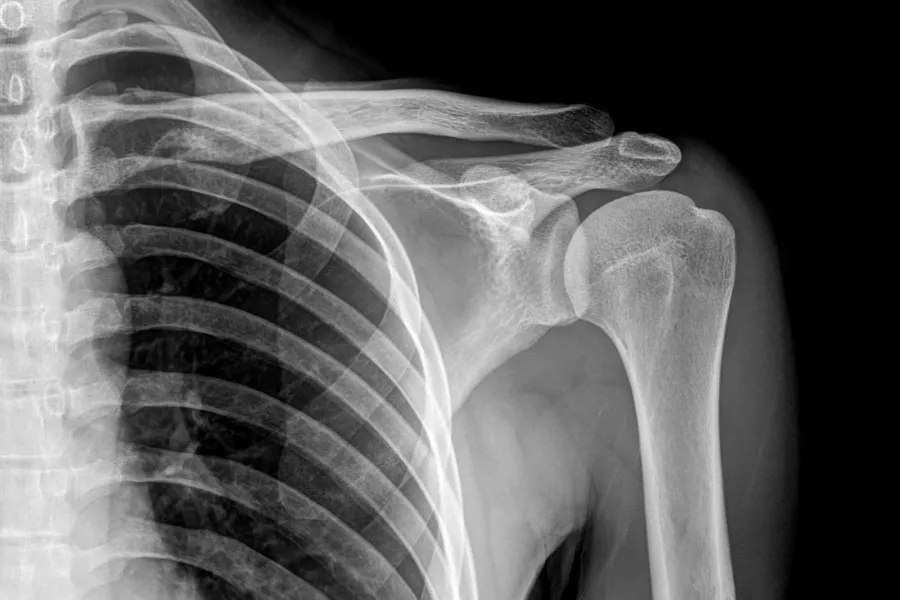

- Diagnostyka opiera się na badaniach obrazowych, takich jak RTG.

Diagnostyka sklerotyzacji stropu panewki opiera się głównie na badaniach obrazowych. Techniki takie jak RTG są niezwykle istotne, ponieważ mogą ujawniać charakterystyczne zmiany sklerotyczne oraz inne objawy degeneracyjne. Wczesne rozpoznanie może znacząco wpłynąć na wybór odpowiedniego leczenia.

RTG | Obrazowanie stawów w celu identyfikacji zmian sklerotycznych. |